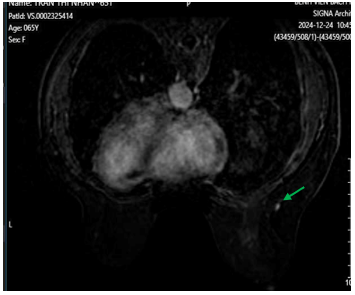

- Cộng hưởng từ tuyến vú có tiêm tương phản: Hình ảnh đám ngấm thuốc trung tâm vú phải, không tạo thành khối, dài 43mm, vùng tổn thương 15x15mm, trung tâm tổn thương dưới núm vú 22mm, nhưng tổn thương ngấm thuốc tới tận núm vú, núm vú ngấm thuốc mạnh (BIRADS 6). Tổn thương chưa xâm lấn cơ thành ngực. Hạch trong nhu mô vú phải vị trí 8h, cách núm vú 6cm, kích thước 4x6mm,ngấm thuốc từ từ tăng dần. Không thấy bất thương vú trái (BIRADS 1).

Hình 3:

Hình ảnh cộng hưởng từ tuyến vú có tiêm tương phản. Hình ảnh đám ngấm thuốc trung tâm vú phải đã lan tới núm vú (BIRADS 6) (mũi tên màu xanh dương).

Hình 4: Hình ảnh cộng hưởng từ tuyến vú có tiêm tương phản. Hình ảnh Hạch trong nhu mô vú phải vị trí 8h (BIRADS 3) (mũi tên màu xanh lá).